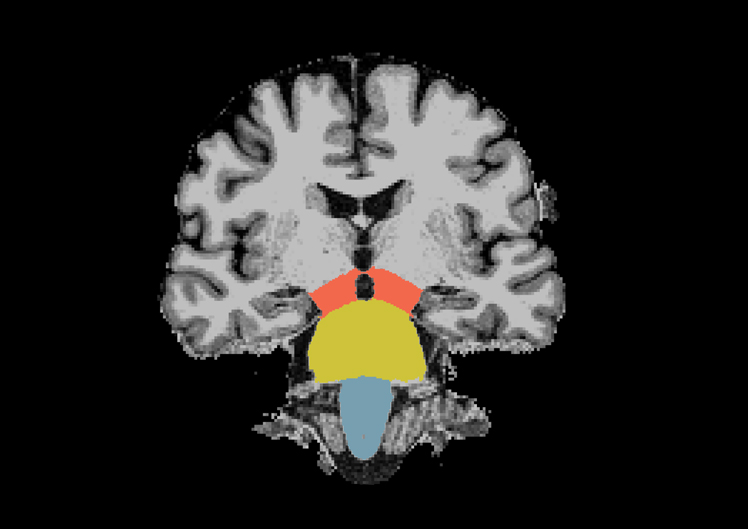

His current research focus is to study Iron overload in Substantia Nigra (SN) using Quantitative Susceptibility Mapping (QSM) and R2* mapping and to quantify Substantia Nigra (SN) damage in Idiopathic rapid eye movement.....